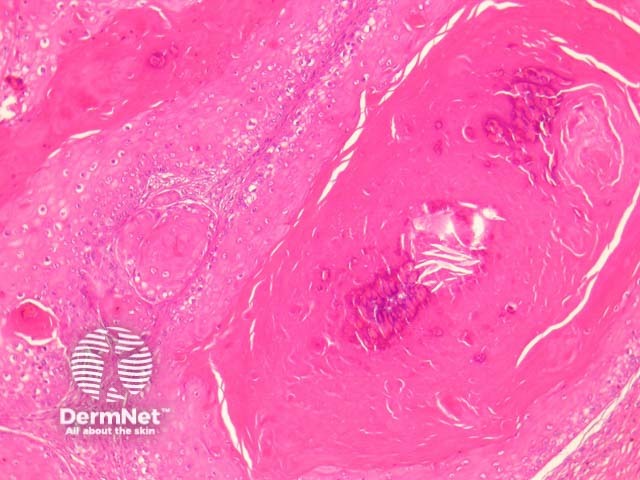

The individual cystic islands resemble regular trichilemmal cysts and often calcify (figure 2). Rupture is common, and this leads to surrounding fibroplasia and foreign body giant cell reaction (figure 3). The lining epithelium is a stratified squamous epithelium exhibiting trichilemmal keratinization (figure 4).

Figure 2